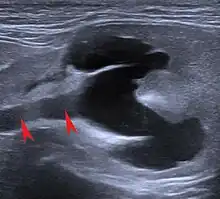

Echographie

L'échographie permet de visualiser plus finement l'architecture du parenchyme rénal. Outre les modifications de taille et de forme, on peut détecter des kystes rénaux, des malformations, des lésions inflammatoires ou tumorales, des urolithiases, etc. Néanmoins, si l'échographie peut permettre d'identifier des lésions rénales, elle ne permet pas forcément d'en identifier la cause[27]. Au moyen de l'échographie doppler pulsée, on peut aussi mettre en évidence des anomalies vasculaires[28],[29].